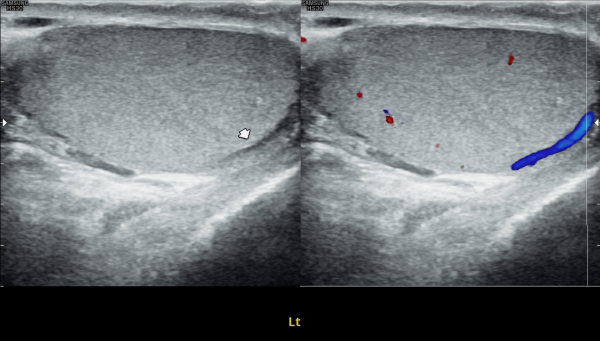

첫 내원 당일 검사한 고환의 초음파 사진상 앉아서 생활하는 직업상 고환 동맥의 순환 장애로 죽상동맥경화증의 소견을 보여 식이요법과 운동요법을 말씀드리고 정관의 표적 치료를 시작한 사진입니다.

On the day of your first visit, the testicular ultrasound showed signs of reduced blood flow in the testicular artery, likely from long hours of sitting. This may have caused early signs of atherosclerosis. We discussed healthy lifestyle changes, including diet and exercise, and started targeted treatment for the vas deferens.

4개월 동안 정관의 표적 치료와 직장 생활중 장시간 앉은 업무를 개선하여 운동을 겸한후 추적 고환의 초음파 사진장

고환동맥의 축상경화증 소견이 치료되고 있는 사진입니다.

This follow-up scrotal ultrasound image, taken after four months of targeted treatment for the vas deferens and lifestyle improvements including reduced prolonged sitting during office work and regular exercise, shows improvement in axial arteriosclerosis of the testicular artery.